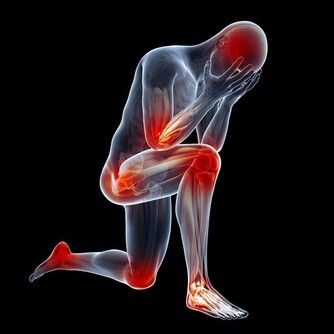

爬樓梯或爬山屬於負重運動,腰部以下的關節都要承受自己身體的重量,尤其膝蓋受力最多。

當身體爬階向上時,膝蓋負擔的重量會瞬間增為平常的4倍左右。

以一個體重60公斤的人為例:平路行走時,兩邊膝蓋各承重60公斤。

爬樓梯或爬山時,膝蓋負重瞬間變成240公斤,相當於左右膝蓋上各扛了一架鋼琴。

而且,速度越快,對膝蓋產生的壓力就越大。

而且,這種對膝蓋的磨損是不可修復的!磨損如果過度嚴重,只能夠置換關節!